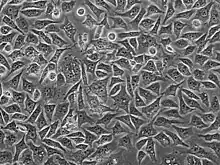

PC3 (PC-3) is a human prostate cancer cell line used in prostate cancer research and drug development.[1] PC3 cells are useful in investigating biochemical changes in advanced prostate cancer cells and in assessing their response to chemotherapeutic agents. PC3 cells are also used to study viral infection in mammalian cells that exhibit an immune response.[2]

The PC3 cell line was established in 1979 from bone metastasis of grade IV of prostate cancer in a 62-year-old Caucasian male.[3] These cells do not respond to androgens, glucocorticoids or fibroblast growth factors,[4] but results suggest that the cells are influenced by epidermal growth factors.[5] PC3 cells can be used to create subcutaneous tumor xenografts in mice to investigate the tumor environment and therapeutic drug functionality.[6]

PC3 cells have high metastatic potential compared to other pancreatic cells of DU145 cells, which have a moderate metastatic potential, and to LNCaP cells, which have low metastatic potential. Comparisons of the protein expression of PC3, LNCaP, and other cells have shown that PC3 is characteristic of small cell neuroendocrine carcinoma.[4]

PC3 cells have low testosterone-5-alpha reductase and acidic phosphatase activity, and do not express PSA (prostate-specific antigen). Furthermore, karyotypic analysis has shown that PC3 are near-triploid, having 62 chromosomes. Q-band analysis showed no Y chromosome. From a morphological point of view, electron microscopy revealed that PC3 cells show characteristics of a poorly-differentiated adenocarcinoma. They have features common to neoplastic cells of epithelial origins, such as numerous microvilli, junctional complexes, abnormal nuclei and nucleoli, abnormal mitochondria, annulate lamellae, and lipoidal bodies.